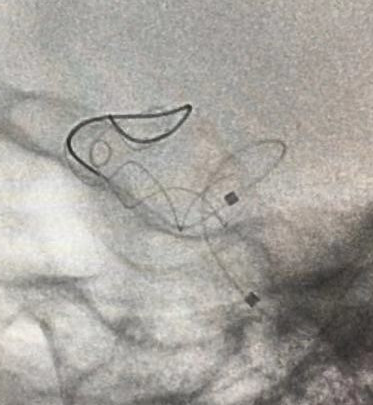

Tubridge®血管重建装置专用支架导管T-track到位,引入4.0mm*30mm支架。

准确定位后,锚定支架头端,缓慢推送支架的同时控制支架张力,顺利释放支架。

为进一步确保Tubridge®血管重建装置完美贴壁,上J型导丝支架内“按摩”。

多角度确认支架已完全贴壁。

正侧位造影示动脉瘤内造影剂明显滞留,载瘤动脉通畅,血流导向作用显著。

术后即刻: